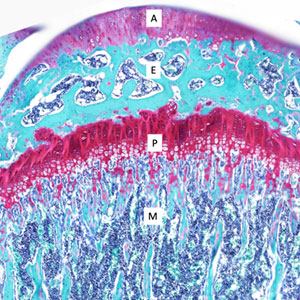

"Satisfaction of Search" Never Stop Looking -- Before and After Surgery

Current Concept Review

Daniel Y. Hong, Stephanie N. Moore-Lotridge, John J. Block, Hernan Correa, Jennifer L. Halpern, Ginger E. Holt, Christopher Stutz, Jeffrey E. Martus, Tim Schrader, Jonathan G. Schoenecker